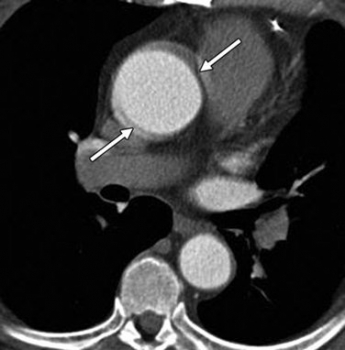

Hình 12. Ngách màng ngoài tim. Hình axial cho thấy ngách màng ngoài tim (mũi tên) giống vành bóc tách ở động mạch chủ lên.